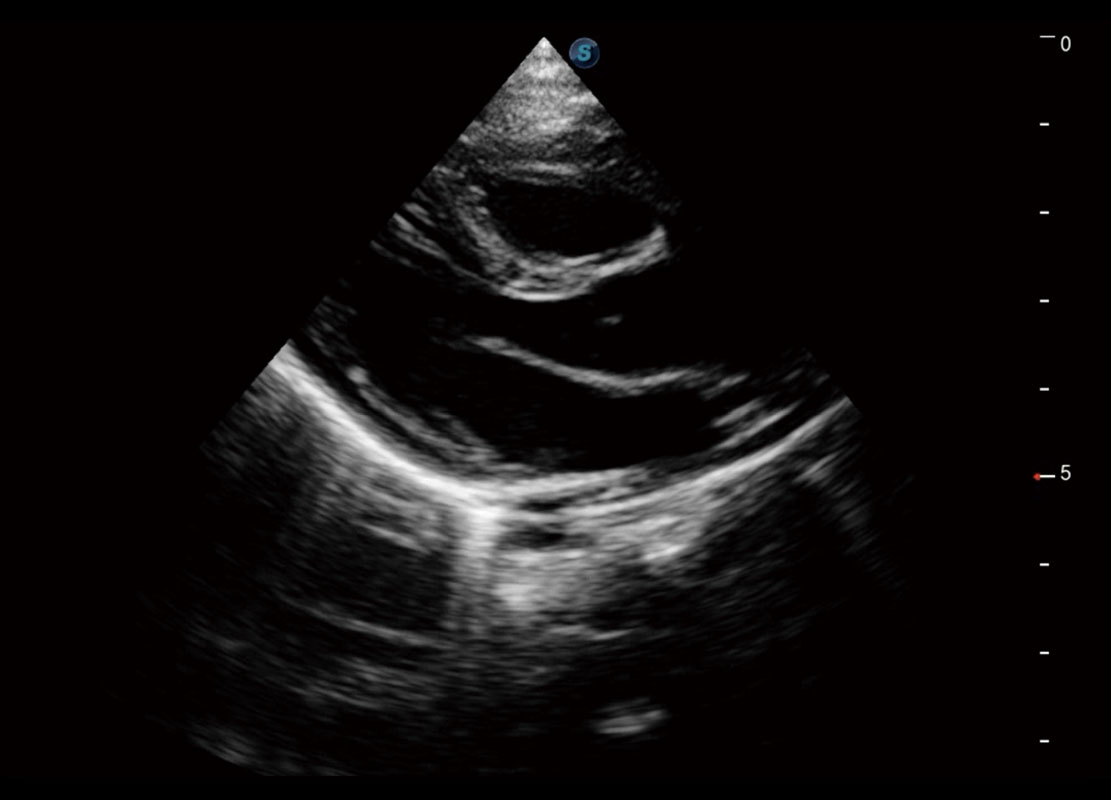

P60在胎兒早孕期超聲篩查中為您帶來(lái)優(yōu)異的圖像質(zhì)量。

早孕-胎心

高分辨率容積成像-早孕胎兒

胎兒體循環(huán)

光影成像-孕囊